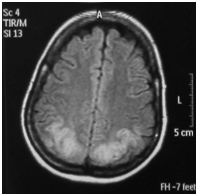

A Computed Tomography (CT) scan of the brain without contrast was done which showed low attenuation areas in bilateral parieto occipital regions with effaced subarachnoid spaces. Magnetic Resonance Imaging (MRI) of the brain depicted T2 weighted image (T2W1) symmetrical cortical high signals in the bilateral parieto occipital cortex and subcortical white matter (Figures 2) (Figure 3), suggesting Posterior Reversible Encephalopathy Syndrome (PRES). Magnetic Resonance Angiography (MRA) and Magnetic Resonance Venography (MRV) turned out to be normal.

Figure 3 (Axial view): MRI of brain Showing T2W1 and FLAIR symmetrical cortical high signals in bilateral parieto-occipital cortex and subcortical white matter.

Posterior reversible encephalopathy syndrome has been reported frequently all over the world.7–9 It is a neurological condition which is diagnosed on the basis of clinical and radiological signs. The clinical features include confusion, seizures, headache and visual disturbances. Investigations such as magnetic resonance imaging usually reveal hyper intense signals at cortical and subcortical areas of posterior distribution (Figures 1) (Figure 2) but other areas such as frontal lobe, brainstem, basal ganglia and cerebellum may also be involved.10,11 There are three notable patterns of posterior reversible encephalopathy syndrome i.e. holohemispheric, superior frontal sulcus and primary parietal-occipital; all of these follow the watershed areas of distribution between major cerebral arteries.12 Although Diffusion-Weighted Magnetic Resonance Imaging (DW-MRI) is of great value in detecting infarcts early on and differentiating vasogenic from cytotoxic edema, it was not available in our hospital.13